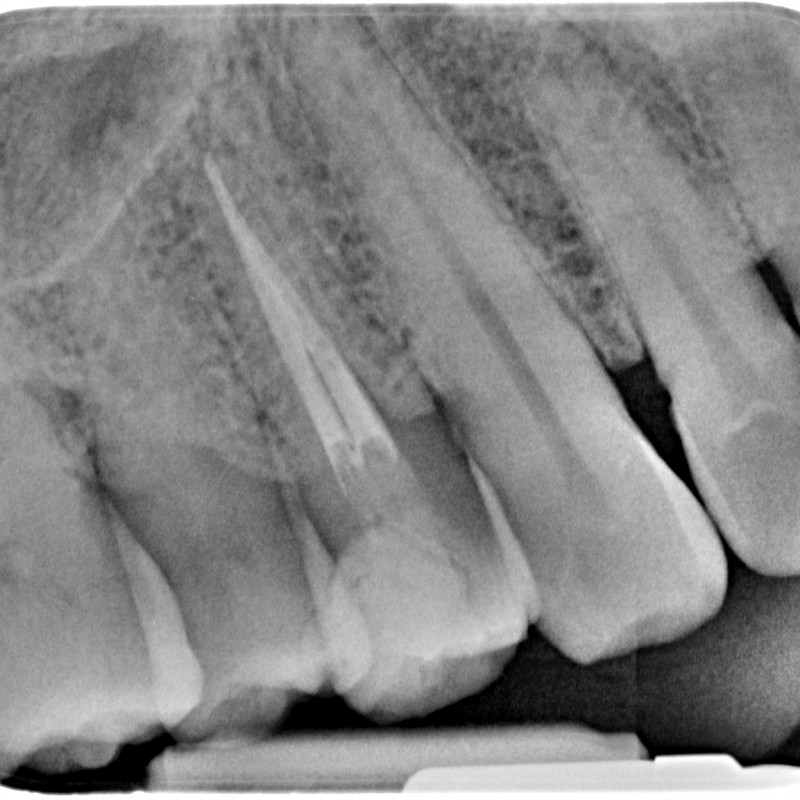

Root Canal Treatment With Microscope